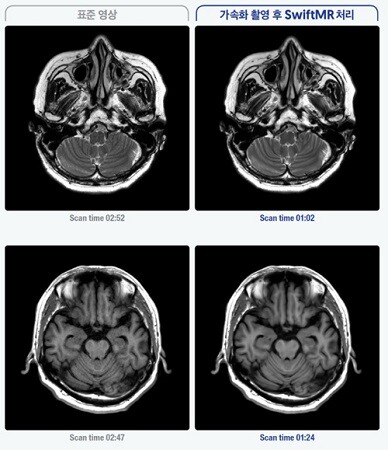

| ▲에어스메디컬 SwiftMR 솔루션 적용 후 촬영 시간 단축과 품질향상 된 모습 (사진=에어스메디컬 제공) |

SwiftMR은 가속 촬영한 MRI 이미지를 딥러닝 기술을 기반으로 복원해 촬영시간은 최대 50% 단축하면서 영상 품질은 기존보다 향상시켜주는 소프트웨어 솔루션이다. 해당 제품은 클라우드 기반의 단독형 소프트웨어로, 별도 하드웨어 설치 없이 의료기관의 PACS(의료영상저장전송장치)와 연동 후 작동 가능하다. MRI 장비 교체, 혹은 추가 구매 없이 30~40분에 이르는 기존 MRI 촬영 시간을 단축할 수 있다. 업체는 이런 점에서 병원의 효율적 MRI 장비 운영 및 수익성 향상과 더불어 환자경험 개선에 도움을 줄 것으로 기대된다고 밝혔다.